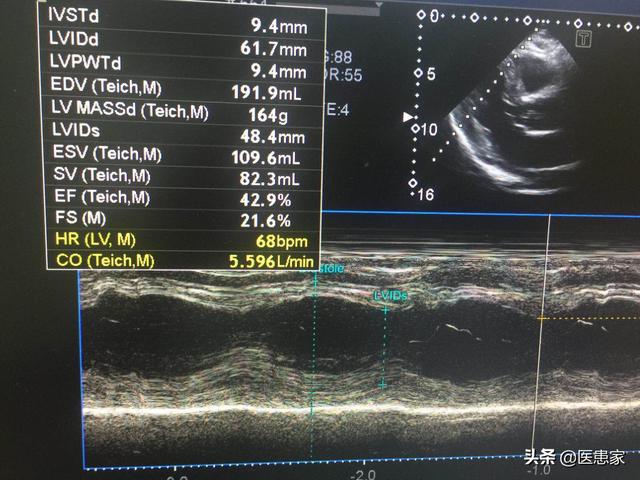

L'infarctus est une nécrose qui survient à la suite d'une occlusion aiguë des artères coronaires, entraînant une ischémie et une hypoxie continues des cardiomyocytes. Après un infarctus aigu, surtout le premier jour, l'activité électrique des cardiomyocytes est très instable, et des arythmies malignes telles que la tachycardie ventriculaire et la fibrillation ventriculaire peuvent facilement se produire, voire une mort subite, qui est la cause la plus fréquente de décès par infarctus. Par conséquent, les patients souffrant d'une crise cardiaque aiguë doivent tous être alités dans une unité de soins intensifs et faire l'objet d'une surveillance cardiaque, ce qui permet de réduire le risque de mort subite.

Si la taille de l'infarctus est trop importante, des complications graves telles que le choc cardiogénique et l'insuffisance cardiaque gauche aiguë peuvent survenir, et la mort peut également survenir si le patient n'est pas secouru à temps. Dans certains cas, des conditions graves telles qu'une rupture cardiaque peuvent survenir, et il n'y a pas de retour possible.

Même si la vie est sauvée par l'anticoagulation et la thérapie antiplaquettaire, un remodelage myocardique peut se produire dans le myocarde nécrosé, entraînant des complications telles que l'insuffisance cardiaque et la tumeur de la paroi ventriculaire, qui affecteront la qualité de vie à l'avenir. Par conséquent, les patients ayant subi un infarctus et dont l'état hémodynamique est stable devraient prendre des médicaments tels que l'IECA pour inhiber le remodelage du myocarde le plus tôt possible.